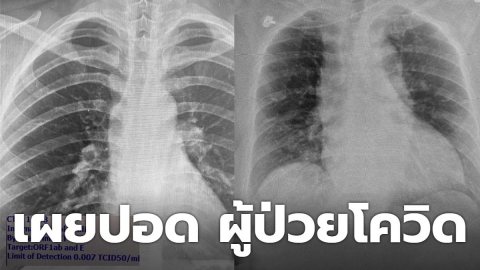

"นพ.โอภาส" เผย ฟิล์มเอกซเรย์ปอด ผู้ป่วยโควิด พบปอดอักเสบหนักติดเชื้อโควิด แต่ไม่มีอาการ